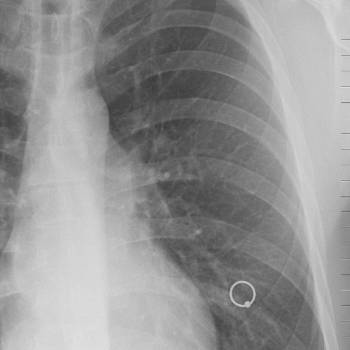

갑자기 살이 빠지는 이유 7. 만성 폐쇄성 폐질환(COPD)

COPD는 만성적인 폐 질환으로, 호흡 곤란과 체중 감소를 유발할 수 있습니다. COPD 환자들은 호흡이 어려워짐에 따라 식사량이 감소하고, 신체가 산소를 효율적으로 사용하지 못하여 에너지 소비가 증가합니다. 이는 체중 감소로 이어집니다. 또한, COPD 환자들은 종종 피로감과 활동 제한을 경험하며, 이는 체중 감소에 기여할 수 있습니다.